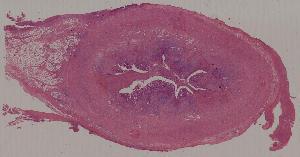

19.蜂窝织性阑尾炎